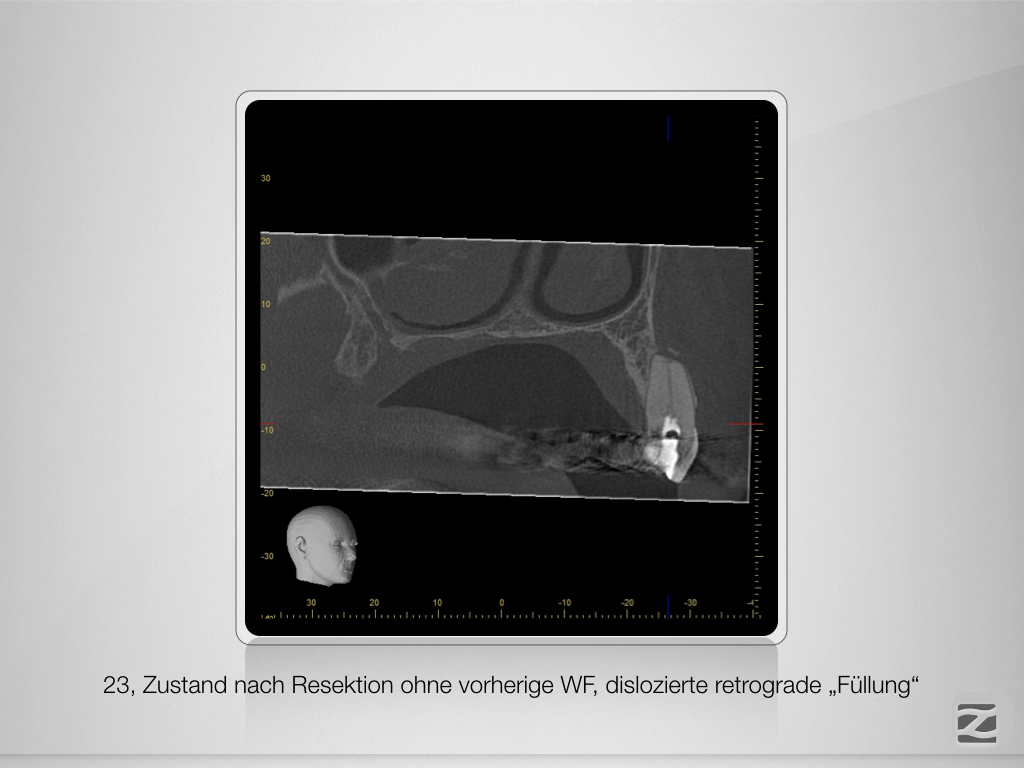

16,15,23 D.013

Wie sag‘ ich’s nur dem Kinde?